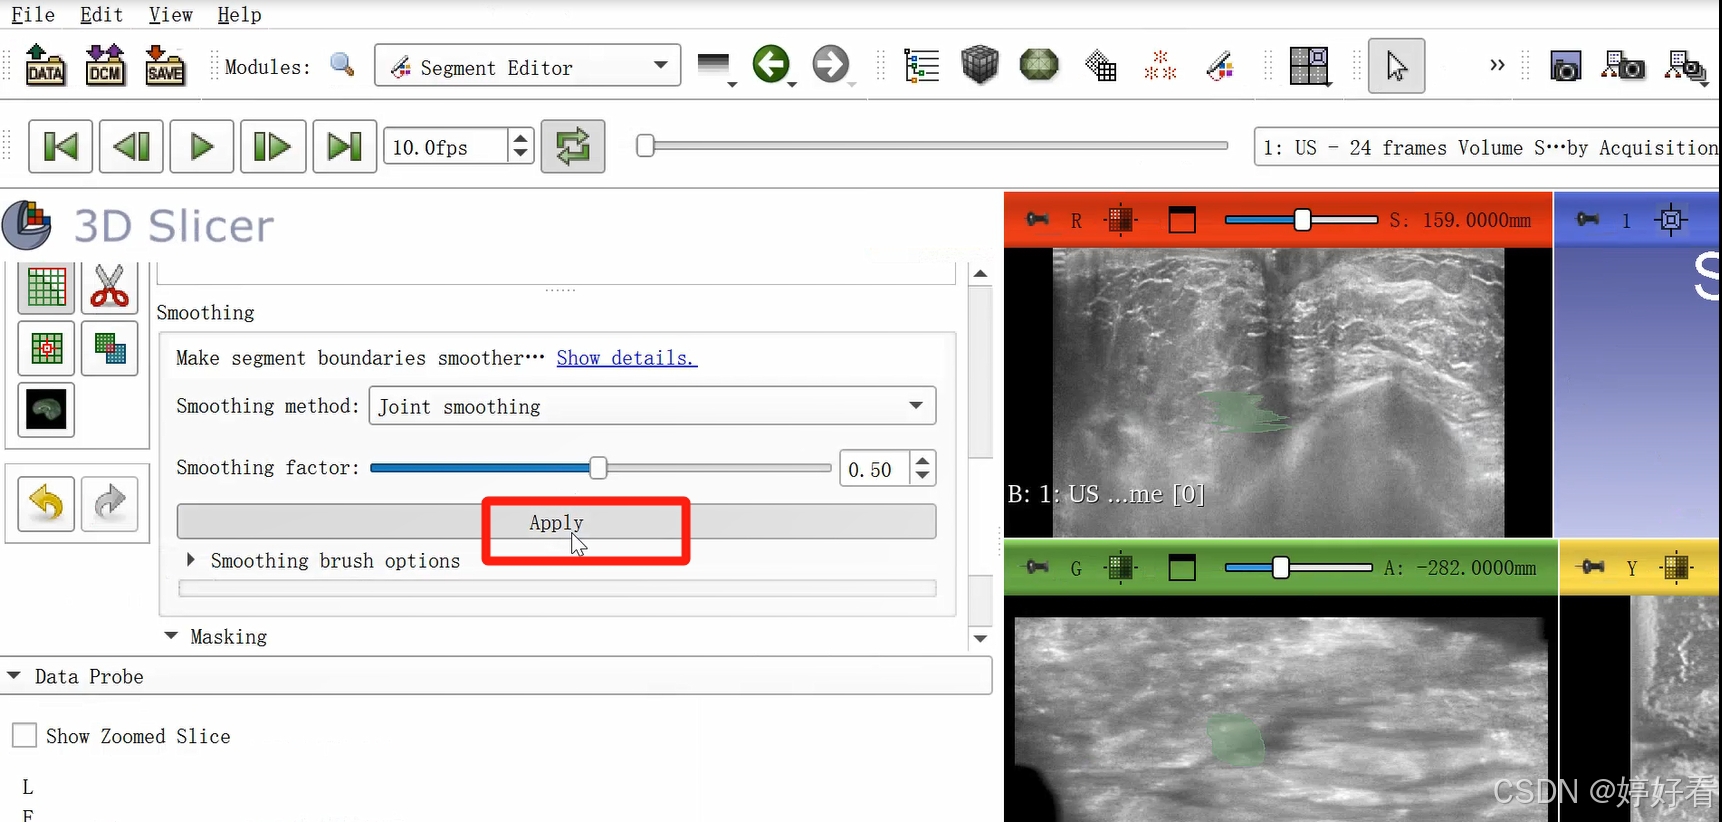

2.7 Smoothing功能使图像表面更光滑

首先,选中Smoothing功能,然后选择Joint smoothing,最后点击Apply。